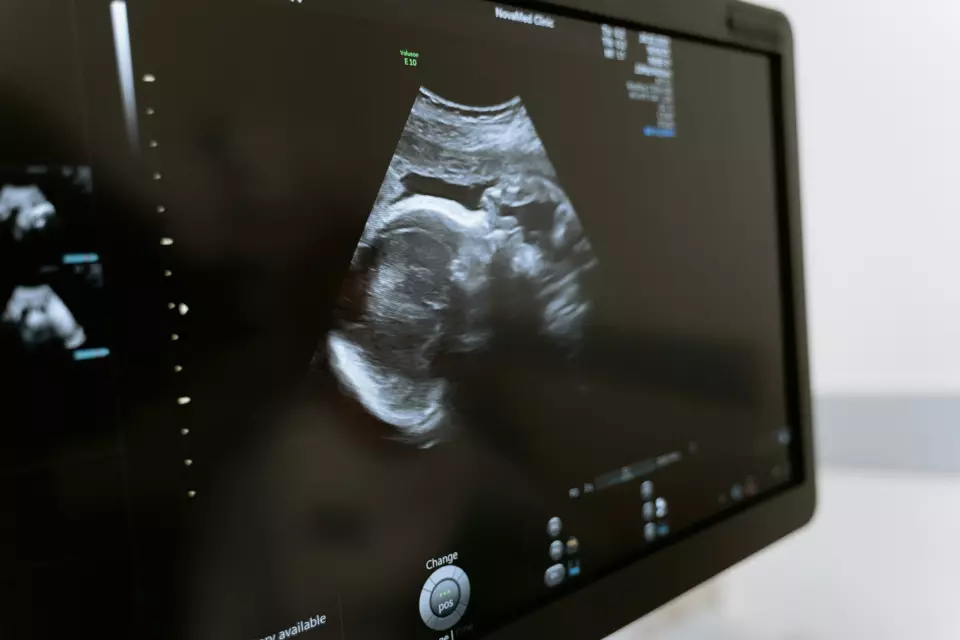

👶 Redovne ultrazvučne preglede

💠 Trudnički pregledi i ultrazvuk

Koristimo modernu dijagnostičku opremu i tehnologiju, kako bi svaka analiza, pregled i ultrazvuk bili tačni, brzi i bez stresa. Naš cilj je da svaka žena zna tačno šta se dešava i kako da se osjeća sigurno u svakom koraku pregleda.